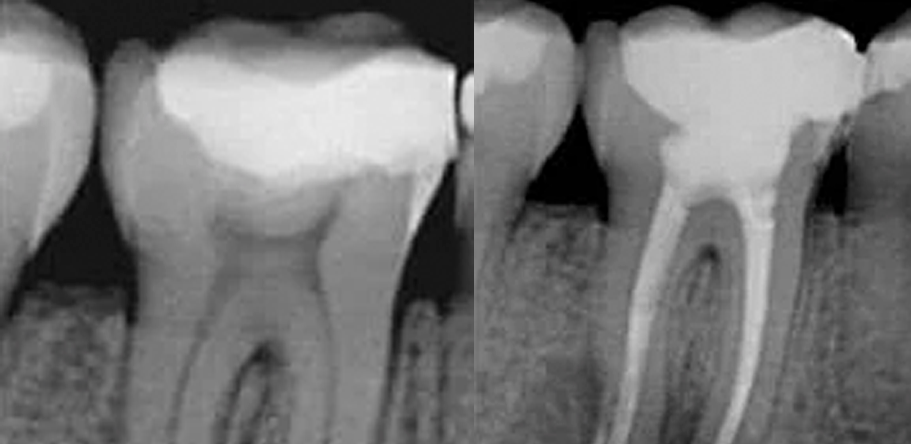

Es un procedimiento dental diseñado para tratar infecciones o daños dentro de un diente. Implica la extracción de la pulpa dental (el tejido blando dentro del diente que contiene nervios y vasos sanguíneos), seguido de la limpieza, desinfección y sellado de los conductos radiculares. Este tratamiento es recomendado cuando la caries esta cerca del nervio y es necesario cuando la pulpa se daña o se infecta a causa de caries profundas, su objetivo es salvar el diente y prevenir su extracción.